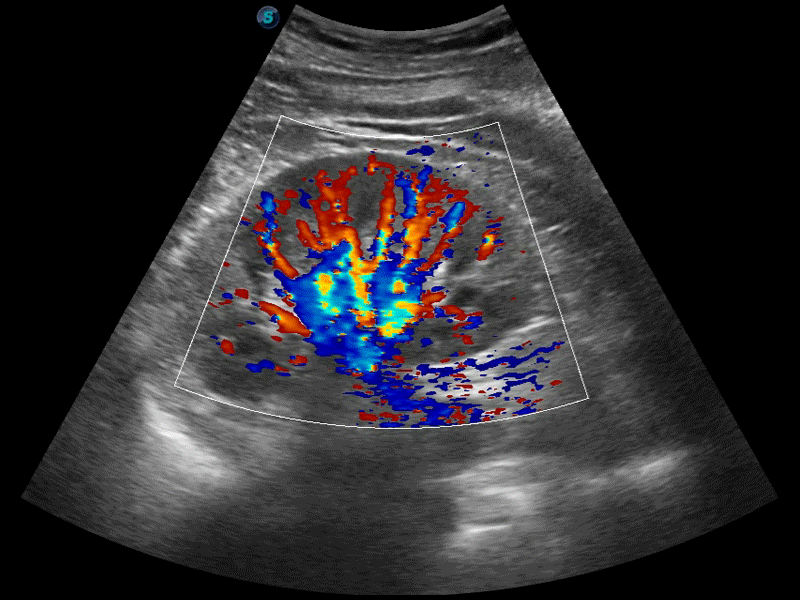

高分辨率血流成像技術(shù)提高了對(duì)低速血流信號(hào)的檢測(cè)能力。在提高空間分辨率的同時(shí),也克服了血流外溢現(xiàn)象,為用戶提供更加真實(shí)的血流動(dòng)力學(xué)信息。

凸陣、線陣和相控陣探頭進(jìn)行實(shí)時(shí)掃描時(shí),開(kāi)啟擴(kuò)展成像模式,可以擴(kuò)展超聲圖像視野,以便更完整地查看大的病灶或組織器官的解剖結(jié)構(gòu)。

通過(guò)色彩血流和實(shí)時(shí)寬景相結(jié)合,可觀察到完整的靜脈或動(dòng)脈的血流,方便醫(yī)生檢查。實(shí)時(shí)掃查過(guò)程中,如有任何操作失誤也可以很容易地進(jìn)行回掃擦除,而不會(huì)中斷掃查。